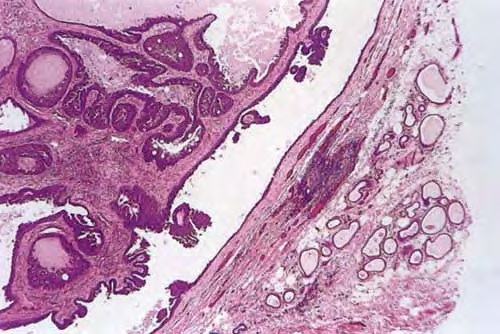

Hidradenoma papilliferum = الغدوم العرقي الحليمي